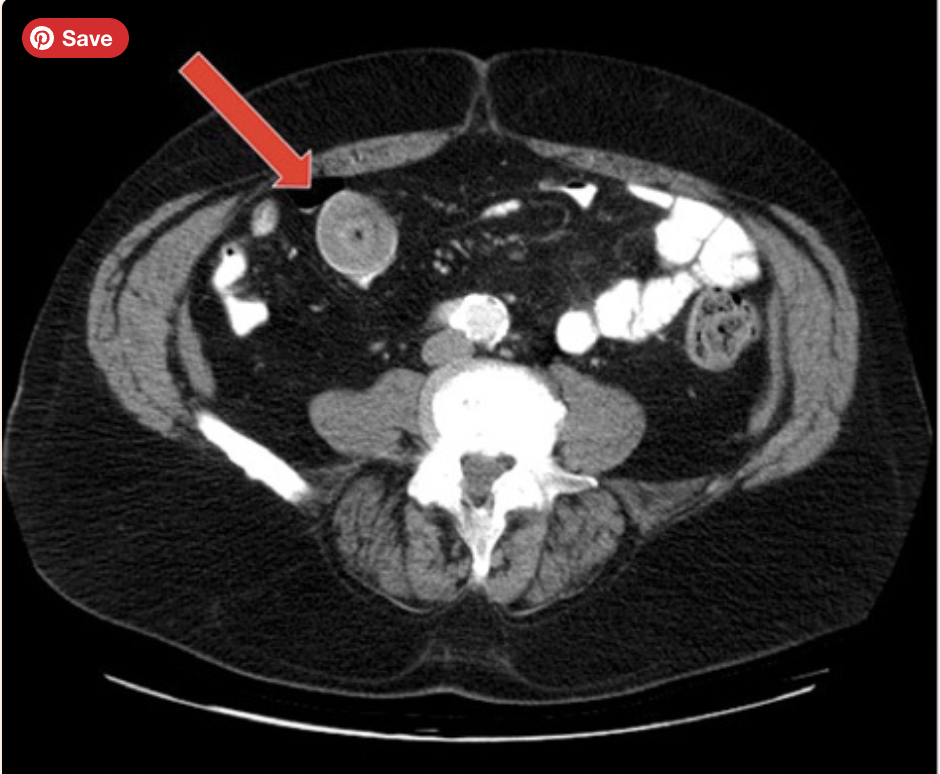

volvulus

Whirl sign